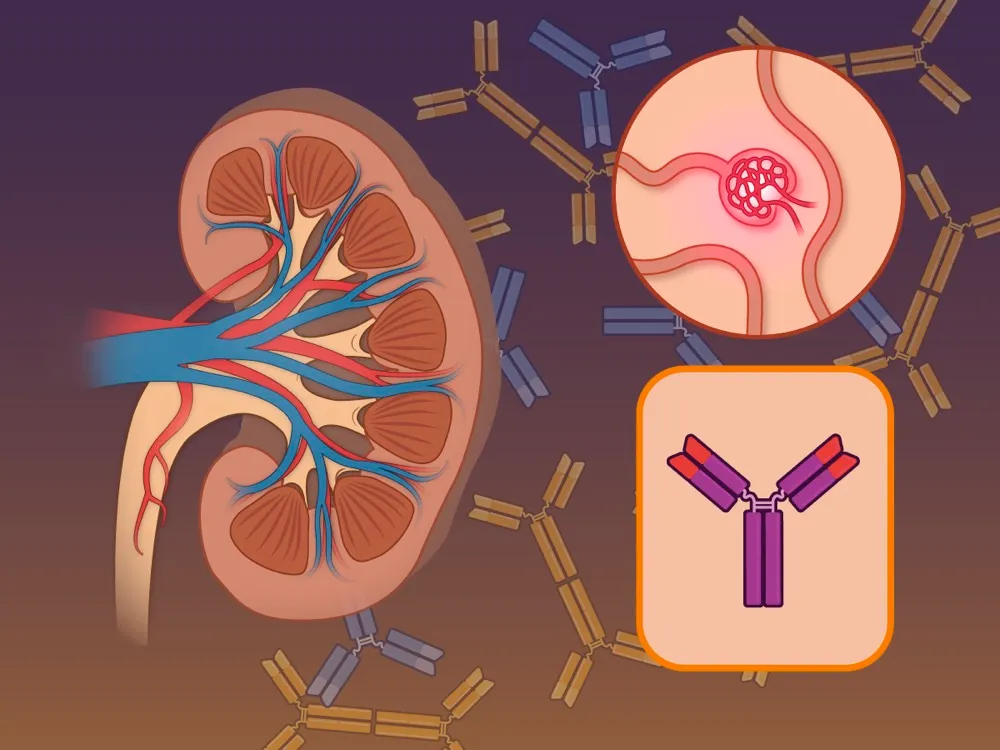

Injúria Renal Aguda (revisão Lancet 2025)

Injúria Renal Aguda (revisão Lancet 2025)